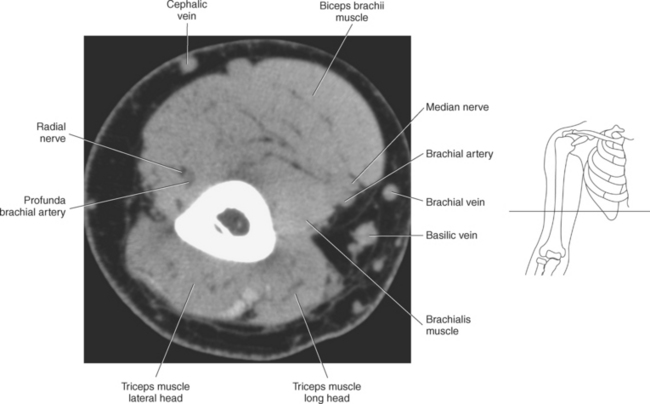

The muscles of the upper arm can be divided into ventral and dorsal groups according to their position. The ventral group contains the biceps brachii, brachialis, and coracobrachialis muscle, and the dorsal group consists of the triceps brachii and anconeus muscles. These muscles are demonstrated in Figures 9.55 through 9.69 and described in Table 9.4.

The triceps brachii muscle is located on the posterior surface of the humerus and is the main extensor of the forearm. Its name triceps is associated with three heads of proximal attachment (long, lateral, and medial). The long head of the triceps originates from the infraglenoid tubercle of the scapula, the medial head originates from the entire dorsal surface of the humerus distal to the radial groove, and the lateral head arises from the dorsal surface and lateral intermuscular septum of the humerus. All three heads join in a common tendon that inserts on the olecranon process of the ulna and the posterior joint capsule (Figure 9.68). The small, triangular anconeus muscle originates on the lateral epicondyle and crosses obliquely to insert on the dorsal surface of the olecranon process, close to the tendon of the triceps brachii (Figure 9.69). It assists the triceps brachii in extension and also provides dynamic joint stability to the lateral joint capsule. For images of the upper arm, see Figures 9.57 through 9.67.

The primary arteries supplying the shoulder region include the axillary and brachial arteries (Figures 9.34 through 9.45 and 9.144, A). The axillary artery begins at the lateral border of the first rib as a continuation of the subclavian artery. It ends at the inferior border of the teres major muscle, where it passes into the arm and becomes the brachial artery. The axillary artery and its branches supply blood to numerous thoracic and shoulder structures, including the first and second intercostal spaces, axillary lymph nodes, mammary gland in women, and scapular, serratus anterior, pectoral, latissimus dorsi, deltoid, and triceps brachii muscles. The branches of the axillary artery typically include the superior thoracic, thoracoacromial, lateral thoracic, subscapular artery, and anterior and posterior humeral circumflex arteries. The brachial artery is the principal arterial supply to the arm. It courses inferiorly on the medial side of the humerus then continues anterior to the cubital fossa of the elbow. The brachial artery is relatively superficial and palpable throughout its course. It accompanies the median nerve, which crosses anterior to the artery in the middle of the arm. During its course, the brachial artery gives rise to numerous muscular branches, which include the profunda brachii, superior ulnar collateral, and inferior ulnar collateral arteries (Figure 9.144, A).

The veins of the upper arm include the brachial, cephalic, and basilic (Figure 9.146). The two deep brachial veins ascend the arm, one on either side of the brachial artery. The brachial veins begin in the elbow from the union of the ulnar and radial veins and end in the axillary vein near the lower margin of the subscapularis muscle. The two deep brachial veins may join to form one brachial vein during part of their course. The superficial veins of the upper arm include the cephalic and basilic. The cephalic vein courses from the radial side of the dorsal venous arch of the hand and then ascends to the midpoint of the forearm, where it curves around to the ventral surface of the forearm and ascends the lateral aspect of the upper arm, along the anterolateral border of the biceps brachii muscle, to open into the axillary vein, just below the clavicle. It drains the superficial parts of the lateral hand and lateral forearm. The basilic vein originates from the medial end of the dorsal venous arch of the hand. It then ascends the ulnar side of the forearm, along the medial surface of the biceps brachii muscle, in the upper arm, to form the axillary vein. The basilic vein drains the superficial parts of the medial side of the hand and medial side of the forearm. The large axillary vein lies on the medial side of the axillary artery. It extends from the lower border of the teres major muscle to the lateral surface of the first rib to continue as the subclavian vein. The axillary vein receives tributaries that correspond to the branches of the axillary artery (Figures 9.34 through 9.47).